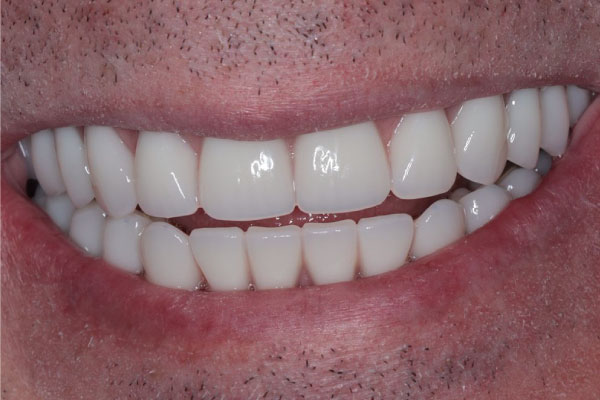

Имплантация зубов: фото "До" и "После"

Фото ДО

Фото ПОСЛЕ

Наведите для просмотра

All-on-4